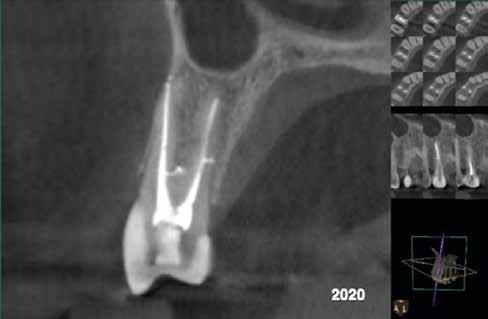

Krell és Caplan kutatásában 2086 repedt fogat vizsgáltak meg. A vizsgált fogak között leggyakrabban a második alsó nagyőrlőfogak (36%), majd ezt követően az első alsó nagyőrlők (27%), és végül az első felső nagyőrlők (18%) fordultak elő. A kutatási eredményeik szerint a fogbél állapota nem befolyásolta jelentős mértékben a kezelés várható kimenetelét. (Irreverzibilis pulpitis 85%; necrosis 80%; korábban gyökérkezelt 74%). A kimenetel szempontjából ugyanígy indifferens volt a páciensek neme, életkora, a kezelés időpontja, a fog pozíciója, a fog helyreállítása során használt anyag típusa, valamint az érintett fogfelszínek száma. 2014 júliusában egy 45 éves hölgy páciens azzal a panasszal kereste fel a rendelőnket, hogy nagyjából 10 napja egy fájdalmas duzzanat alakult ki a jobb felső első kisőrlője koronája mellett (14). A klinikai vizsgálat során egy amalgámtömést találtunk a panaszos fogban. A tömés széli zárása nem volt megfelelő, a disztális záróléc és a tömés között rést tapasztaltunk. A fog disztobukkális és linguális felszíne mellett 8 mm-es csontos tasakokat mértünk. A periapikális felvételen az 14-es foggyökér disztális felszínének megfelelően vertikális irányú radiolucens felritkulást észleltünk. A klinikai vizsgálat során a mesiális zárólécet kettéválasztó törésvonalat detektáltunk (17–18. ábra). A fogszenzibilitás vizsgálata során negatív eredményt kaptunk. A páciensnek ismertettük az elérhető terápiás lehetőségeket: 1, a 14-es fog eltávolítása, majd a foghiány 3 tagú cementezett híddal történő pótlása; 2, a 14-es fog eltávolítása, kemény- és lágyszöveti augmentáció, majd implantátum behelyezése; 3, a 14-es fog gyökérkezelése, gyökértömése és ezt követően a csücsökborítást biztosító restaurátum készítése. Arra is felhívtuk a páciens figyelmét, hogy a 3. terápiás lehetőség választása esetén nem tudjuk a fogmegtartás sikerességét garantálni, de végül – főként anyagi okok miatt – mégis ezt a terápiás opciót választotta. Fontos megjegyezni, hogy a repedt fogak ellátási lehetőségeit a törésvonal mélysége, elhelyezkedése, lefutása nagyban befolyásolja. A kezelés megtervezése során a fog és a fogat körülvevő szövetek állapotával kapcsolatos számtalan különböző faktort kell egyidejűleg figyelembe vennünk. A gyökérkezelést követően a gyökértömést meleg vertikális kondenzációs technikai alkalmazásával készítettük el (19. ábra). A hozzáférési nyílást folyékony és hibrid kompozit tömőanyag segítségével zártuk. A zárás elkészítése során a dr. David Clark által kifejlesztett Bioclear matricarendszert alkalmaztuk. A 6 éves kontroll során készített (2020) röntgenfelvételen a csontos defektus telődése volt megfigyelhető. Ez is a parodontális defektus gyógyulását igazolta (20–21. ábra).

17. ábra: A 14-es fog gyökerének disztális felszíne mellett vertikális csontpusztulásra utaló jelek észlelhetőek. Klinikailag ezen a területen 8 mm mélységű tasakmélységet mértünk. – 18. ábra: A 14-es fog disztális zárólécének megfelelően törésvonal észlelhető, ugyanakkor a csücskök teljes szeparálódására utaló jelek nem láthatóak. Az amalgámtömés eltávolítását követően jól megfigyelhető volt a törésvonal teljes lefutása. – 19. ábra: A gyökértömés elkészítése során meleg vertikális kondenzációs technikát alkalmaztunk. A felvételeken oldalcsatornák jelenlétére utaló jelek is észlelhetőek. – 20–21. ábra: A 2020-ban készült kontrollfelvételeken jól látható a csontos defektus telődése. A radiológiai jelek alapján (jól lekövethető gyökérhártyarés) a parodontális ligamentumok regenerációját is vélelmezzük.